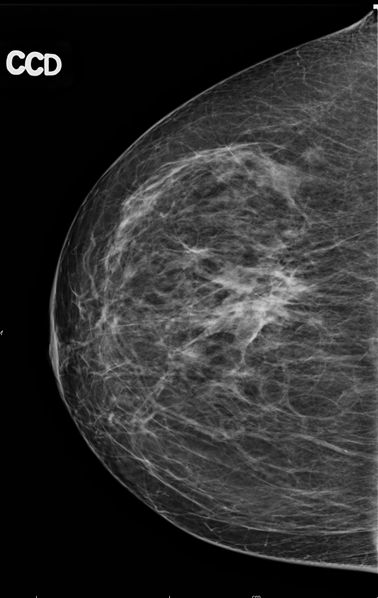

La mammographie est une radiographie des seins. Il s'agit d'une technique d’imagerie médicale qui utilise une faible dose de radiation pour visualiser les structures internes du sein. Cet examen radiologique permet de diagnostiquer plusieurs affections du sein, qu’elles soient bénignes ou malignes, en détectant des changements au niveau du tissu mammaire.

Durant la mammographie, le sein est comprimé afin de réduire la quantité de radiations requises, en diminuant l’épaisseur du tissu mammaire. Cet aspect permet d’obtenir un examen de meilleure qualité, comportant plus de détails et limitant les artéfacts possibles. Il existe deux types de mammographies :

Afin de mieux examiner le sein, plusieurs clichés sont réalisés sous différents angles. La mammographie dure en moyenne 10 à 15 minutes, sauf si des clichés supplémentaires ou d’autres examens complémentaires doivent être réalisés.

Après la mammographie, le radiologue analyse les clichés, vous interroge et pourrait réaliser un examen clinique. Il examine l’aspect de la peau et du mamelon. Il palpe les seins et recherche des ganglions anormaux.

Il n’est pas toujours possible de donner d’emblée un diagnostic définitif : la mammographie permet de voir s’il existe une anomalie dans le sein, mais elle ne permet pas de déterminer avec certitude s’il s’agit ou non d’une image cancéreuse.